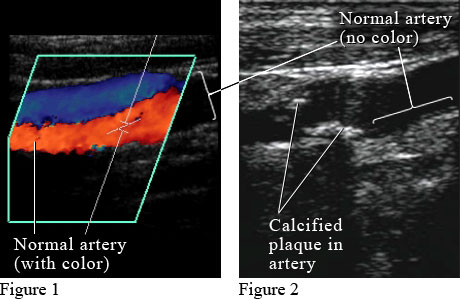

Figure 1 shows a color Doppler ultrasound picture of blood flowing through a normal artery (red) and vein (blue). Figure 2 shows an ultrasound picture of an artery narrowed by the buildup of calcium and fat (cholesterol) in the inner lining of the artery, called plaque, which leads to "hardening of the arteries" (atherosclerosis).